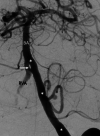

Figure 2. Arteriogram of patient with accessory vertebral artery (left arrow) and left aortic origin of the left vertebral artery (right arrow)

Note that both arteries feed into the intracranial blood supply indicating an anastomosis between the two vessels.